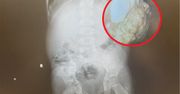

Na przyjęciach urodzinowych, weselach, komuniach, chrzcinach i rozmaitych imprezach utarło się, że pomieszczenia ozdabia się balonami. Takie dekoracje wyglądają wprawdzie pięknie, jednak mogą być śmiertelnie niebezpieczne dla najmłodszych. Szczególnie, jeśli jakiś balon pęknie i dostanie się do przełyku dziecka.